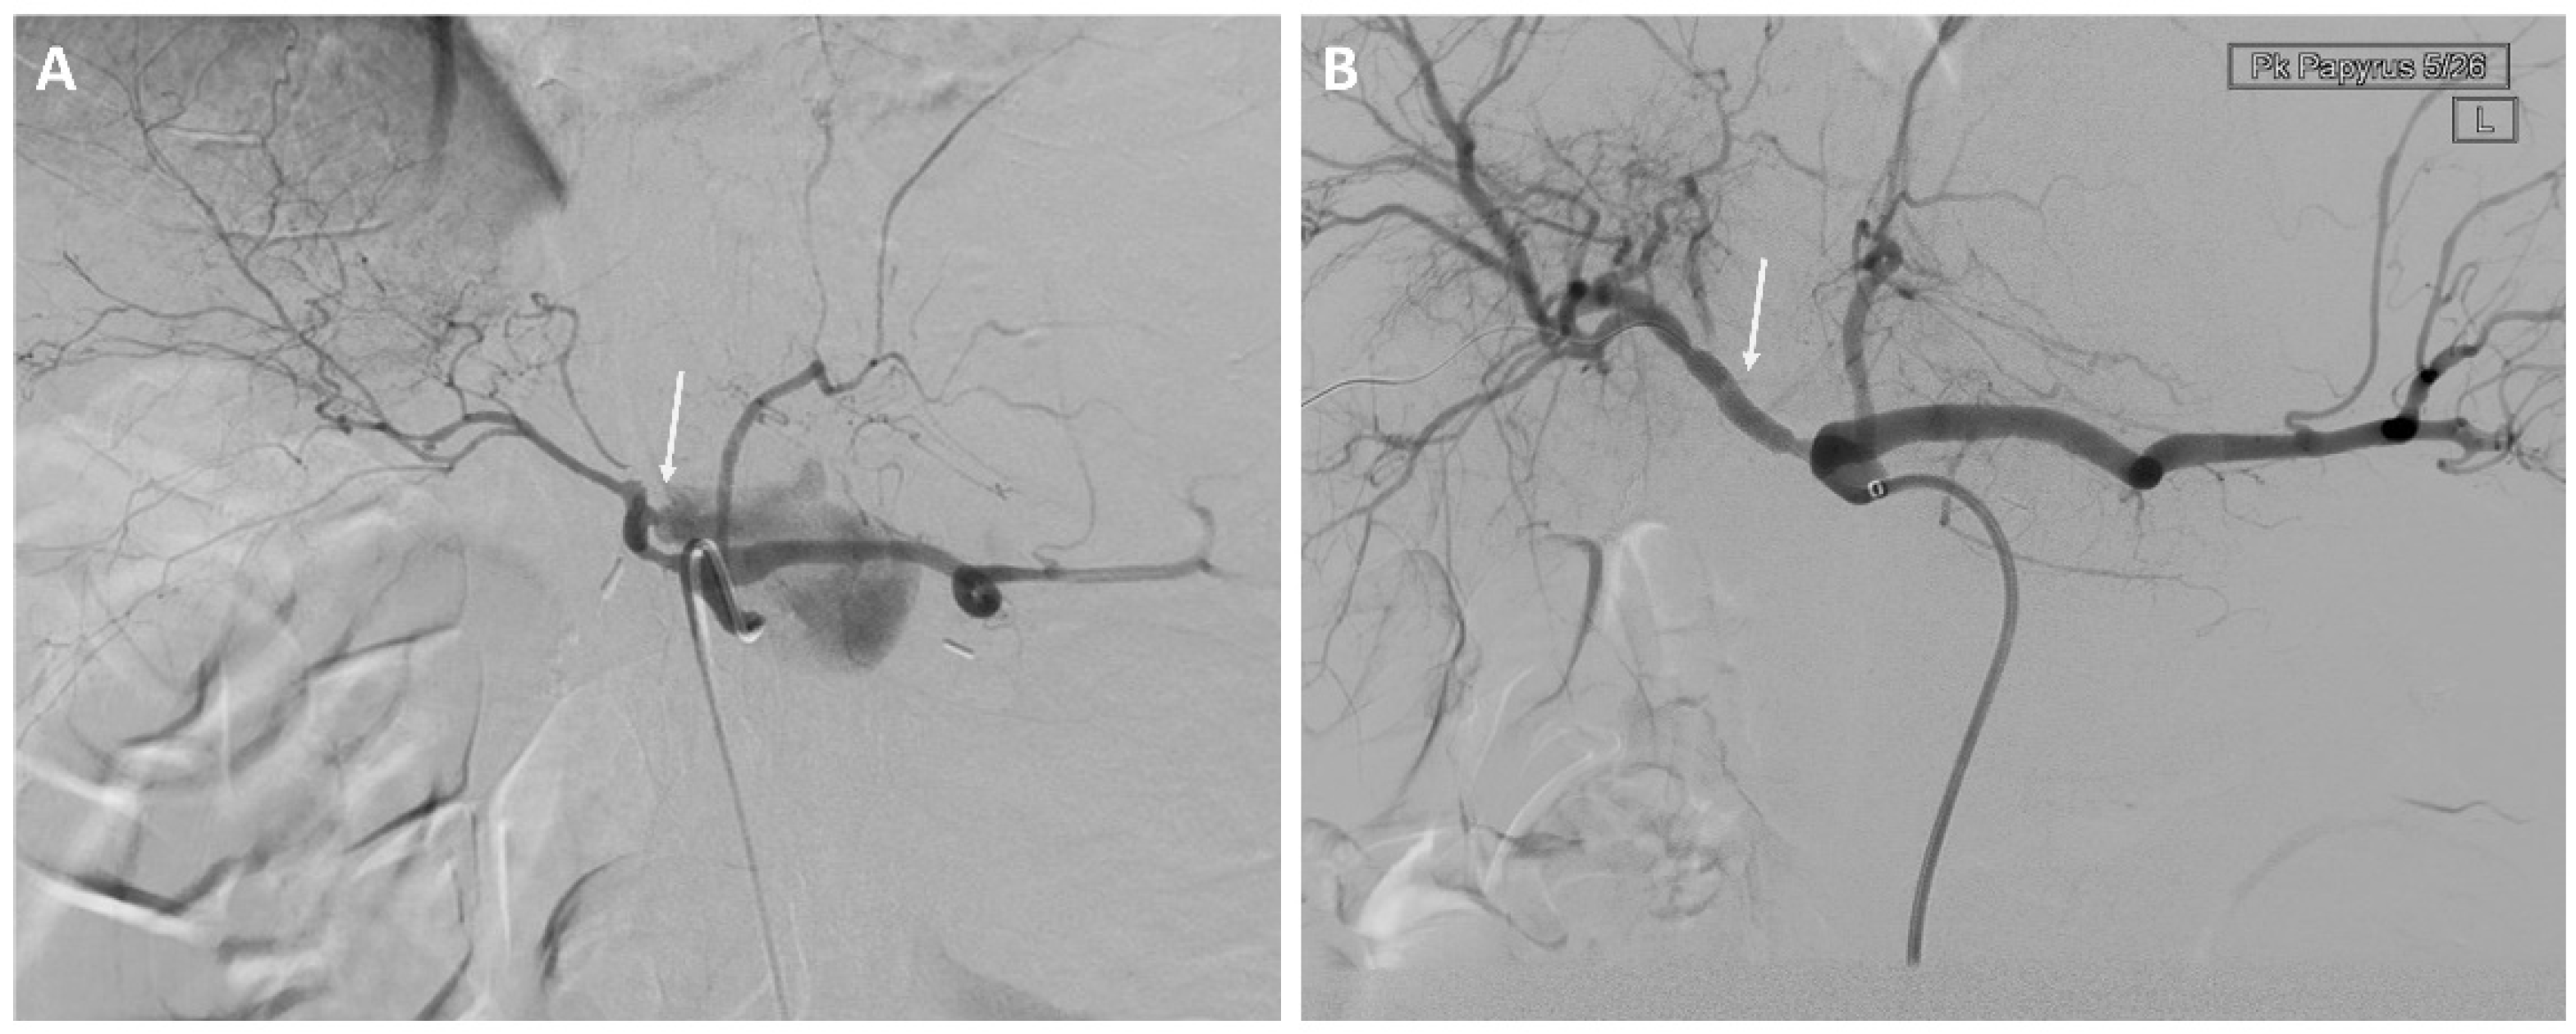

Eight of 37 (22%) patients in the EVT group underwent stent-graft treatment of the eroded vessels: celiac artery (n = 1), common hepatic artery (n = 4) see Figure 1, right hepatic artery (n = 1), and superior mesenteric artery (n = 2) see Figure 2. The stent-grafts used were Advanta V12TM (Getinge, Gothenburg, Sweden) in five patients, PK Papyrus covered stent (BIOTRONIK, Bulach, Switzerland) in one, covered balloon-expandable Jomed stent (Abbott Vascular, Santa Clara, CA, USA) in one, and polytetrafluoroethylene (PTFE)-covered Jostent GraftMaster® (Abbott Vascular, Santa Clara, CA, USA) in one. Technical success was achieved in all cases.

Figure 1.

A 61-year-old man with a history of pancreatic head adenocarcinoma and pylorus preserving pancreatoduodectomy (PPPD). (A) Angiography showing bleeding from the gastroduodenal artery stump and the hepatic artery. (B) Treatment of the hepatic artery with a stent-graft.